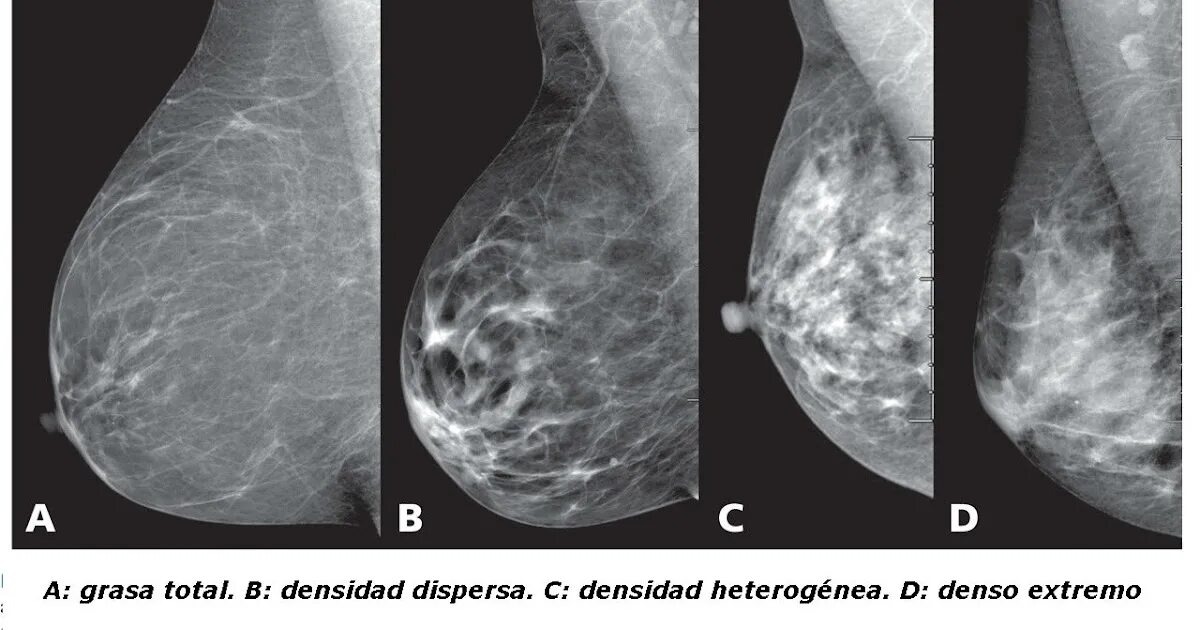

Существует классификация плотности молочных желёз по АСR:

А - наименьшая плотность, много жировой ткани;

В - умеренная плотность;

С - неравномерно плотная, может скрывать небольшие образования;

D - очень плотная, обычная скрининговая маммография неинформативна.